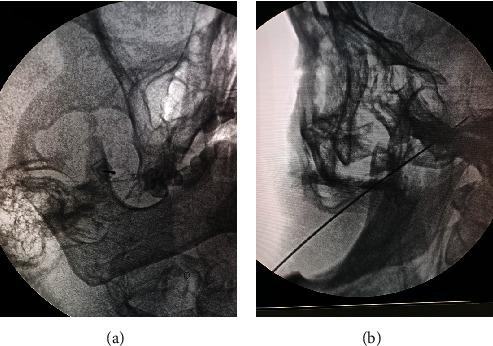

高电压、长时程脉冲射频联合阻滞治疗急性/亚急性带状疱疹相关性三叉神经痛的疗效。

Efficacy of Gasserian Ganglion High-Voltage, Long-Duration Pulsed Radiofrequency Combined With Block on Acute/Subacute Zoster-Related Trigeminal Neuralgia.

Trigeminal postherpetic neuralgia (TPHN) is a severe chronic pain that can lead to various socioeconomic consequences. Therefore, it is necessary to explore optimal treatment options for acute/subacute herpes zoster (HZ)-related trigeminal neuralgia and prevent the further development of TPHN. High-voltage, long-duration pulsed radiofrequency (HL-PRF) of the Gasserian ganglion is a new surgical intervention used to treat PHN. A ganglion block has been reported to possess anti-inflammatory effects and potential analgesic benefits. We included 83 patients with HZ-related acute/subacute trigeminal neuralgia admitted from January 1, 2021, to June 1, 2023, and received Gasserian ganglion HL-PRF combined with block. A 6-month follow-up was conducted, including Numerical Rating Scale (NRS) scores, Pittsburgh Sleep Quality Index (PSQI), the incidence of TPHN, the dosage of anticonvulsants and analgesics, efficacy, and adverse events. All patients showed a significant decrease in postoperative NRS scores ( < 0.05). The NRS scores of the acute HZ group were consistently lower than those of the subacute HZ group at different time points ( < 0.01). The overall incidence of TPHN from the onset of HZ to 12 weeks is 21.68%. The incidence of TPHN in the acute phase group was 12.77%, significantly lower than the 33.33% in the subacute phase group (=0.024). The effective rate was 74.7% in all patients, at 3 months after the treatment. The effective rate was 82.98% in the acute phase group and 63.89% in the subacute phase group, showing a statistically significant difference (=0.047). The PSQI score of the acute group was consistently lower than that of the subacute group ( < 0.01). The dosage of analgesics and anticonvulsants used in the acute HZ group was lower than that in the subacute group ( < 0.01). All patients did not experience serious adverse reactions. Gasserian ganglion HL-PRF combined with block can be an effective and safe technique to relieve the pain of acute/subacute zoster-related trigeminal neuralgia and prevent the incidence of TPHN.

摘要

三叉神经带状疱疹后神经痛(TPHN)是一种严重的慢性疼痛,可导致各种社会经济后果。因此,有必要探索治疗急性/亚急性带状疱疹相关三叉神经痛的最佳治疗方案,并预防 TPHN 的进一步发展。高电压、长时间脉冲射频(HL-PRF)的三叉神经节是一种新的手术干预手段,用于治疗 PHN。已有报道称神经节阻滞具有抗炎作用和潜在的镇痛益处。

我们纳入了 2021 年 1 月 1 日至 2023 年 6 月 1 日收治的 83 例带状疱疹相关急性/亚急性三叉神经痛患者,均接受 Gasserian 神经节 HL-PRF 联合阻滞治疗。进行了 6 个月的随访,包括数字评分量表(NRS)评分、匹兹堡睡眠质量指数(PSQI)、TPHN 的发生率、抗惊厥药和镇痛药的剂量、疗效和不良反应。